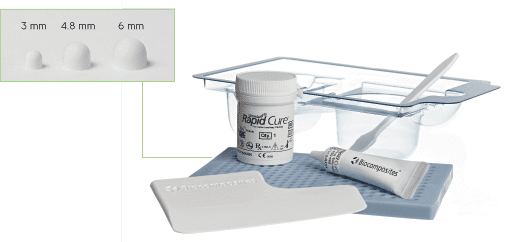

STIMULAN can be used in three sizes of bead, as a paste or for injection, to optimise packing in bone and soft tissue. Its hydrophilic properties and options of rapid or standard setting times make it quick and easy if mixed with one or more antibiotics – helping you to adapt to each case as is merited.*